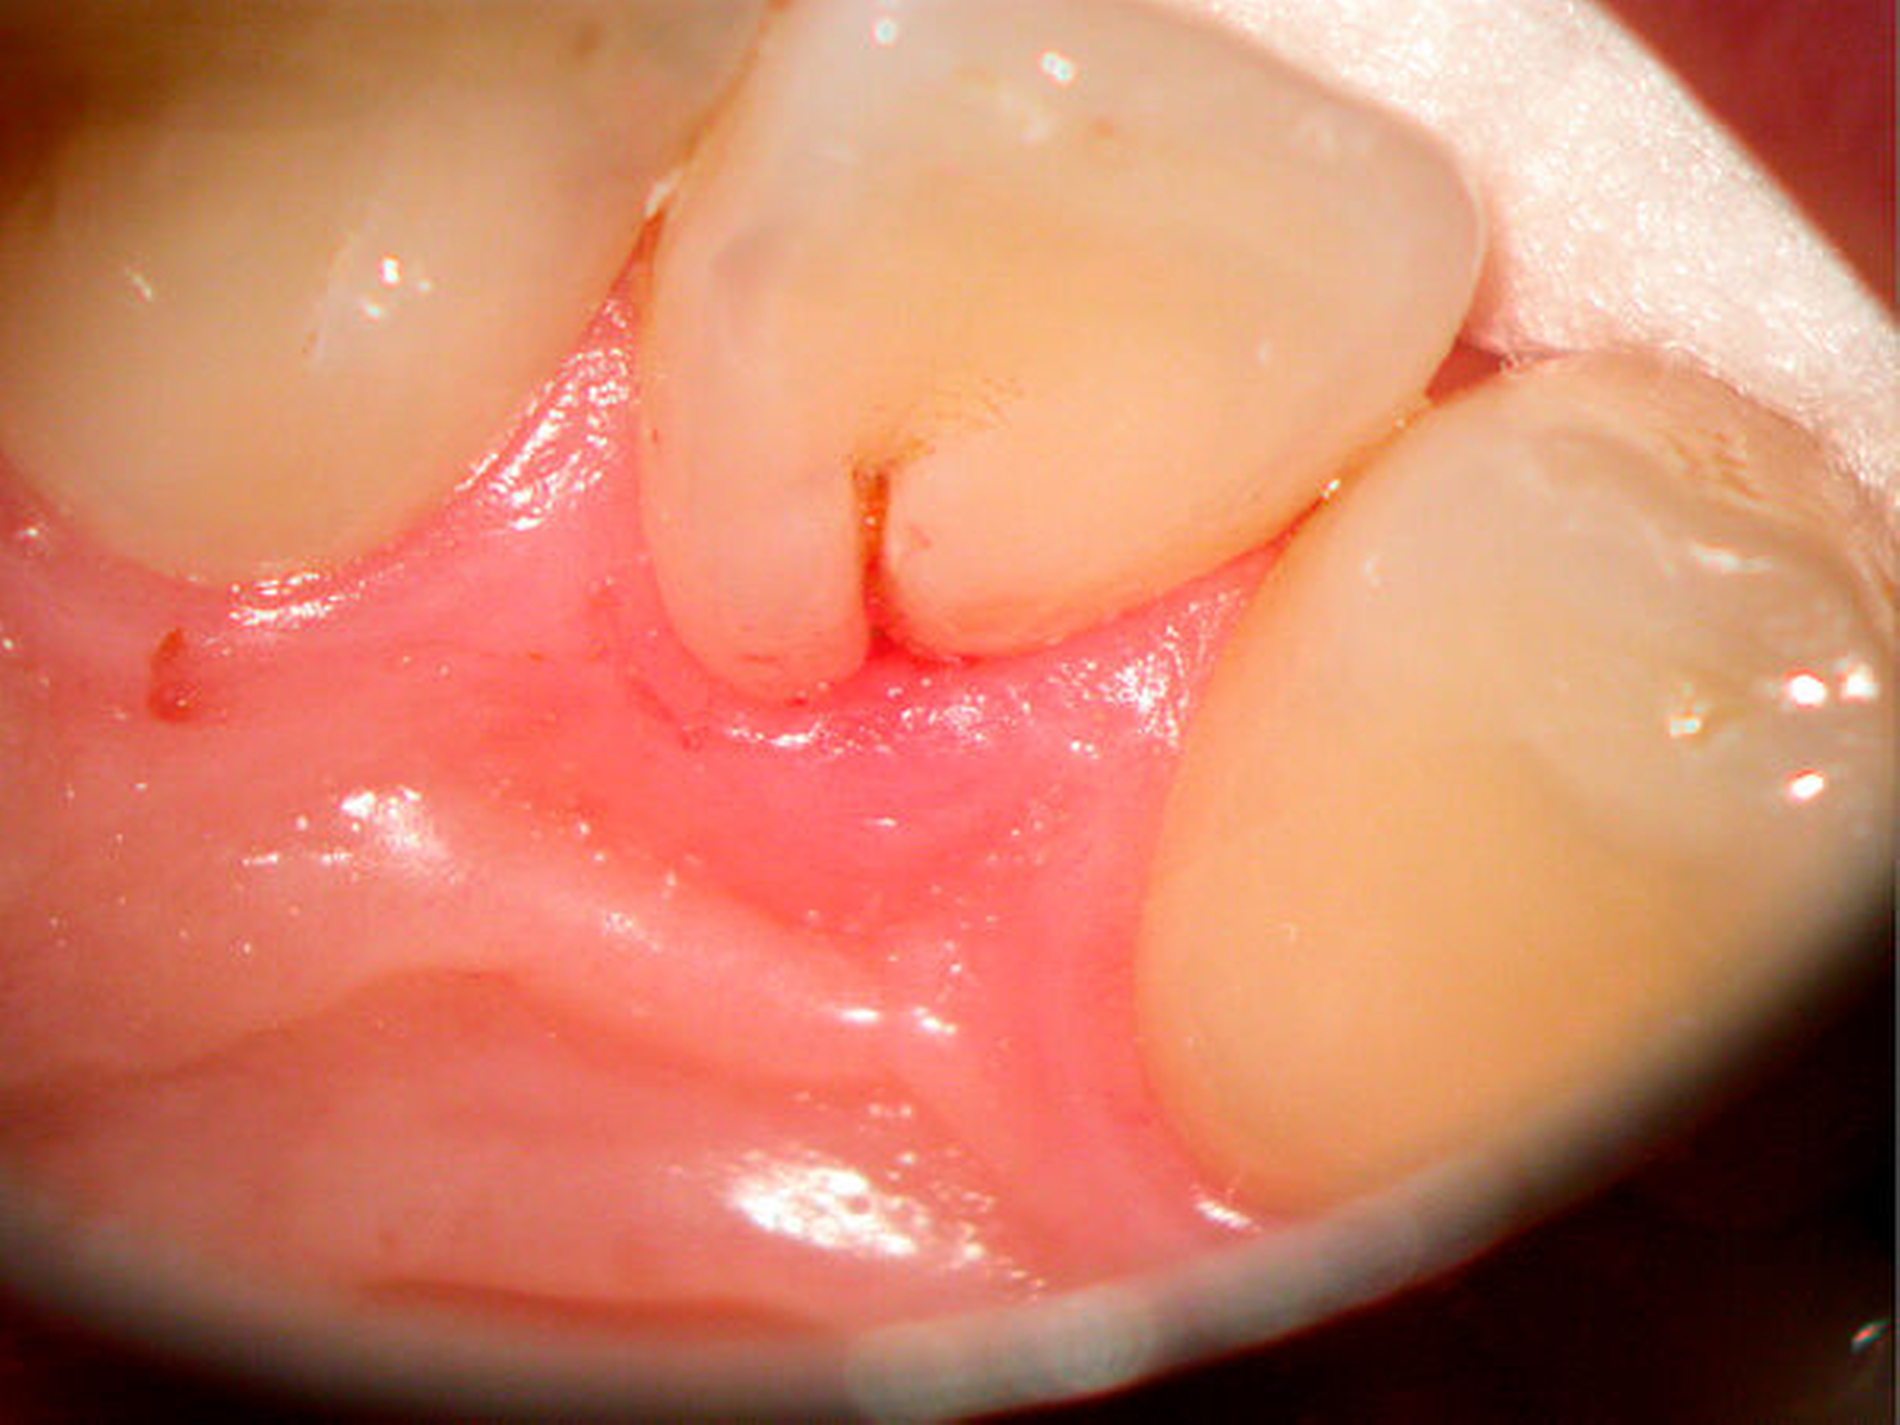

Bei einem ausgeprägten Foramen caecum sollte eine weitere anatomisch-morphologische Variation in die Differenzialdiagnostik – zur Abklärung eventueller anatomischer Besonderheiten – einbezogen werden: In Verlängerung des Tuberculum dentis kann sich eine Fissur über die Schmelz-Zement-Grenze hinaus auf der Wurzeloberfläche fortsetzen. Je nach Ausprägung können diese Wurzelfurchen auch den Beginn von Wurzelseparationen darstellen. Im Ergebnis der Einfaltung des Schmelzepithels und der Einschnürung im Bereich der Hertwigschen Wurzelscheide enwickelt sich in seltenen Fällen eine rudimentäre oder vollständig ausgebildete Wurzel [Black, 1908; Arnold, 2007; Gandhi et al., 2011]. In seltenen Fällen können einwurzelige Zähne mit zwei oder mehr Wurzelkanälen [Kottoor et al., 2012] oder zweiwurzelige Zähne mit zwei Wurzelkanälen auftreten [Fabra-Campos, 1990] (Abbildung 17).

Mit dem Zahndurchbruch und der mikrobiellen Kontamination der zumeist palatinal gelegenen Wurzelfurche kann eine lokalisierte Gingivitis oder Parodontitis begünstigt werden.